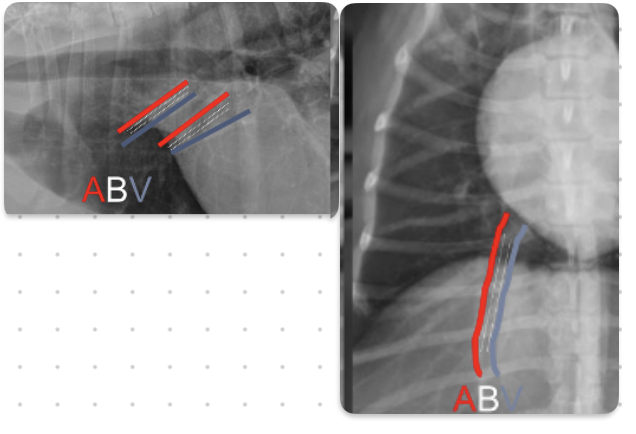

What is the ordering of pulmonary arteries and veins in relation to bronchi

ABV

-veins are ventral and central

-arteries are dorsal and peripheral

What is the general rule on size of pulmonary vessels

-equal to diameter of 9th rib as they cross it

-make sure arteries and veins are about the same size